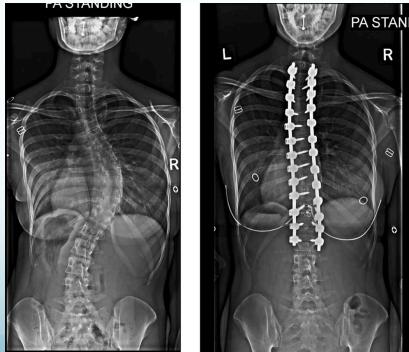

Surgical Treatment

Indications:

- Curves >40° in skeletally immature patients

- Progressive curves

Procedure:

- Correction

- Instrumentation

- Fusion

Surgery

- Adult documented progressive curves